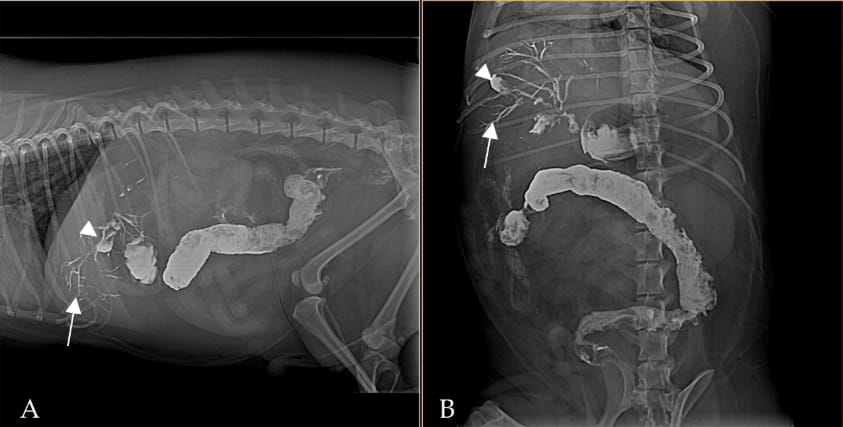

Right lateral (A) and ventrodorsal (B) abdominal radiography at 2 h post-barium. Barium is visible outlining the biliary tree (white arrows) and is beginning to fill the gallbladder (white arrowhead). Residual contrast is also present in the stomach and intestines, and fecal matter mixed with barium is seen in the colon.

Barium contrast imaging demonstrated gradual filling of the biliary system by reflux from the duodenum. CT confirmed pancreatic abscesses, biliary distension, and contrast material within the biliary tree. Ultrasonography revealed pancreatic enlargement, hyperechoic fat stranding, and a distended major duodenal papilla. Exploratory surgery verified multiple pancreatic abscesses and adhesions to the duodenum. Despite intervention, the dog deteriorated and was humanely euthanized. No direct sphincter of Oddi functional testing was performed, but inflammatory disruption of the sphincter was strongly suspected.